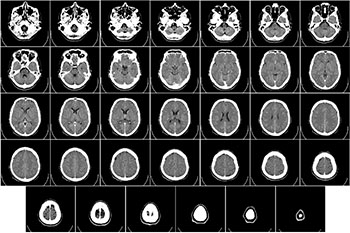

뇌출혈의 전형적인 증상 및 유형

뇌출혈의 전형적인 증상으로는 감각장애, 발열, 고혈압, 운동장애, 뇌정맥 혈전증, 심한 두통, 두개 내 압력 증가, 수막 자극, 탈장 등 입니다. 사례의 일부에서 간혹 발작을 일으켜 눈이 초점을 맞추고 혼동되거나 심한 경우에는 혼수상태가 됩니다.

1. 기저핵의 출혈

피각(Putamen)과 시상(Thalamus)은 고혈압 뇌출혈의 가장 흔한 두 부분으로 내부의 하강 운동 섬유, 상승하는 감각 섬유 및 시각 방사선으로 분리됩니다. 측면(부종) 또는 내측(시상) 확장 혈종은 이 섬유를 억압하여 대측 운동, 감각 기능 장애를 일으키며 일반적으로 병변의 반대측 편마비, 편심 감각의 부족 및 부분 실명 등의 징후와 심한 출혈로 인해 의식장애가 발생할 수 있고 뇌실에 침투시킬 수 있으며 피의 뇌척수액(CSF)이 나타나고 피질에 직접 침투하는 것은 일반적이지 않습니다.

2. 피각 출혈

주로 줄무늬가 있는 동맥의 측방 파열로 더 심각한 운동기능 결함, 지속적인 등방성 혈뇨증, 병변의 반대쪽 시선이 발생할 수 있으며 주요 반구에는 실어증이 생길 수 있습니다.

3. 시상 출혈

시상 발생 동맥과 시상 관통 동맥의 파열로 인해 보다 명백한 감각장애, 일시적 등방성 혈뇨가 발생합니다. 출혈성 초점 억압 피질 언어기관은 실어증을 유발할 수 있으며, 시상 국소 출혈은 독립적으로 나타날 수 있습니다. 실어증 증후군이 나타날 수 있지만 예후가 좋으며, 시상 출혈은 다음과 같은 특징이 있습니다. 상지와 하지의 마비가 같고 깊은 감각 장애가 더 두드러집니다. 다량의 출혈이 중뇌 상부 시각 중심을 손상시키고 안구가 코 끝을 응시하는 것과 같이 아래쪽으로 편향됩니다. 그리고 더 무거운 출혈은 시상 하부로 퍼지거나 세 번째 심실로 쪼개지고 혼수상태가 깊어지며 동공이 줄어들고 장식적인 뻣뻣함이 나타납니다. 이는 기저핵 출혈이라고 하며 시상과 시상이 모두 관련되어 있고 출혈의 시작을 구별하는 것이 어렵습니다.

4. 꼬리핵 뇌출혈

두통, 구토 및 경한 수막 자극, 명백한 마비가 없으며 지주막하 출혈과 매우 유사하고 때때로 눈에 보이는 반대쪽 중앙 안면 마비가 있으며 임상에서 쉽게 무시되지만 두통으로 인한 CT 검사에서 발견됩니다.

5. 엽상 출혈

모야모야 질환, 혈관 아밀로이드증 종양에 의해 발생되며 대뇌 정맥 기형에서 이동되고 두통, 구토, 실어증, 시각 이상, 수막 자극, 간질 발작은 혼수상태보다 더 일반적입니다. 정수리 출혈은 마비 감각장애 및 공간적 형태 장애, 전두엽의 편마비, 기관지 실어증, 손으로 더듬는 증상, 측두엽의 베르니케 실어증, 후두엽 정신 질환이 나타날 수 있습니다.

6. 소뇌출혈

소뇌 동맥의 파열로 인해 몇 분 이내에 발병이 갑작스럽고 두통, 현기증, 빈번한 구토, 심한 후두부 두통 및 균형 장애 등이 발생 하지만 사지 마비가 없으며 질병 시작시의 의식이 명확하거나 경미합니다. 의식이 모호함, 가볍지만 사지의 서투른 성능, 동작 불안정, 운동 실조 및 안진, 심한 출혈은 12~24 시간 내에 혼수상태와 뇌간 압축 징후로 떨어질 수 있습니다. 신경 마비, 눈을 쳐다보면 병변의 반대편 측면보기에서 눈동자는 감소하고 광반응이 존재하며 사지 마비와 병적 반사 작용, 늦은 눈동자 팽창, 중심 호흡기 기능 장애가 있으며 발병 직후의 출혈은 구별하기 쉽지 않습니다.

7. 1차 뇌실내 출혈

뇌출혈의 3%에서 5%를 차지하며 파열된 뇌 실내 합병증이나 심실 동맥의 출혈로 인해 발생합니다. 대부분의 경우는 뇌 실내 출혈로 두통, 구토 및 수막이 보입니다. 지주막하 출혈과 유사한 자극 징후 및 피의 뇌척수액, 무의식적 장애, 국소 신경학적 징후는 완전히 회복 될 수 있으며 예후는 양호합니다. 많은 양의 뇌실내 출혈은 갑작스런 발병을 일으켜 빠르게 혼수상태, 사지의 이완성 마비, 뻣뻣함, 빈번한 구토, 작은 동공, 눈알의 곁눈질 또는 부양 등의 증상과 함께 상태가 위중하고 사망이 빠른 것이 특징입니다.